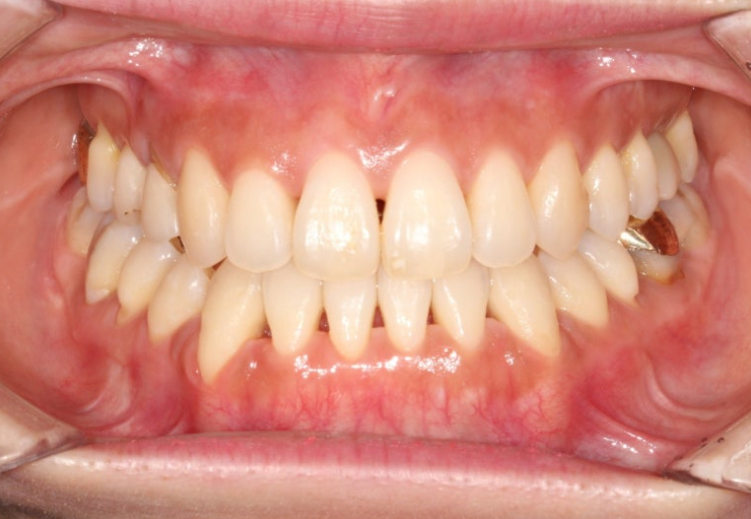

24.01~25.07

삐뚤 앞니는 가지런해졌습니다.

이제 전후 비교 보겠습니다. 총 치료기간은 1년 반, 재제작은 1회 했습니다.

앞니 뿐만 아니라 어금니 반대교합도 함께 개선되었습니다.

중심선은 개선되었습니다.